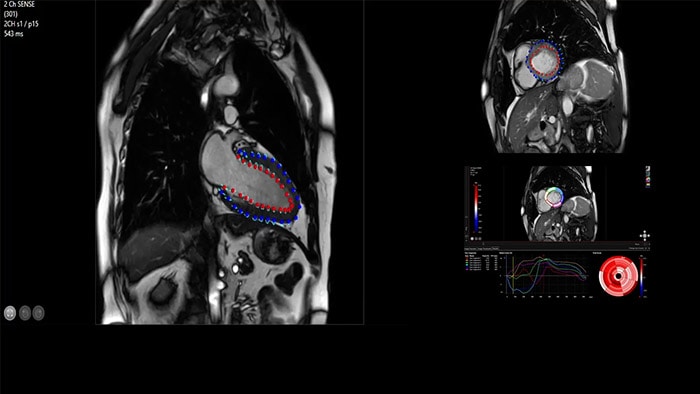

IntelliSpace Portal ofrece una suite integral de resonancia magnética cardíaca, que proporciona flujos de trabajo dedicados para análisis funcional, viabilidad, LGE, evaluación de mapeo cardíaco y análisis funcional de VD/VI en menos de 5 minutos por caso3.

La adición de Compressed SENSE a sus exámenes cardíacos reduce el tiempo que el paciente pasa en el escáner de resonancia magnética y permite la reducción de los tiempos de retención de la respiración mientras mantiene una calidad de imagen prácticamente igual6. Compressed SENSE es aplicable tanto a adquisiciones 2D como 3D.

IntelliSpace Portal MR Caas(7,8) Strain(9) ayuda en el diagnóstico y monitoreo del paciente al proporcionar parámetros de deformación global como la deformación longitudinal global (GLS), la tensión circunferencial global (GCS) y la tensión radial global (GRS), mediante imágenes de RM de eje corto y largo, así como también al describir la deformación del miocardio, como el acortamiento, el engrosamiento y el alargamiento durante el ciclo cardíaco.